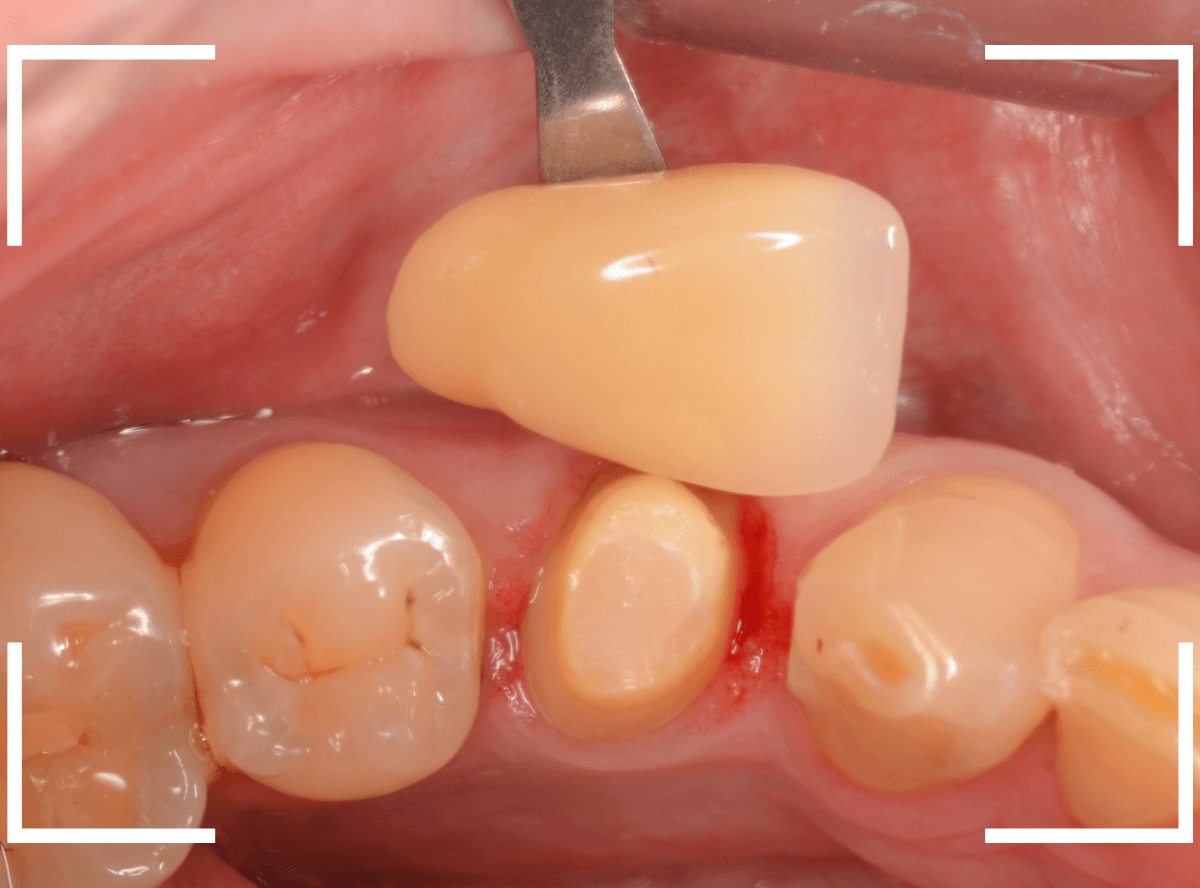

ファイバーコアをsetし、歯の周りの歯肉が落ち着くまで、仮歯を入れて様子を見ます。

頃合いをみて、歯の型をとってさし歯の製作に移ります。

今回は、オール・ジルコニア・クラウンで製作することになりました。

最終setした状態です。

今回は厳しい条件でしたが、なんとか最終setまでする事ができました。